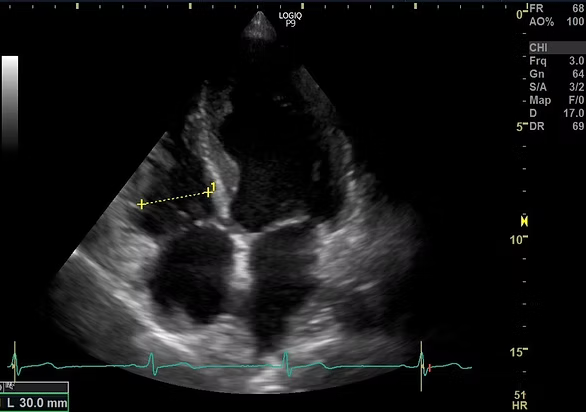

頸動脈エコー、心臓エコー、下肢静脈エコーの検査を行っています。頸動脈エコーは首の中にある頸動脈を観察し、動脈硬化のために血管が傷んでいないか、血液の流れが悪くなっていないかを調べる検査です。心臓エコーは心臓の大きさや心臓の筋肉の動きを観察することによって、心臓のポンプ機能が働いているかを調べます。下肢エコーは太ももからくるぶしにかけて静脈の流れが悪くなってないかを調べる検査です。いずれの検査も痛みのない、手軽で安全な検査です。

心臓エコー